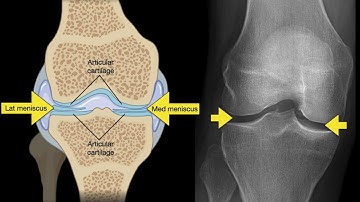

Leg X Ray AP view and LT View